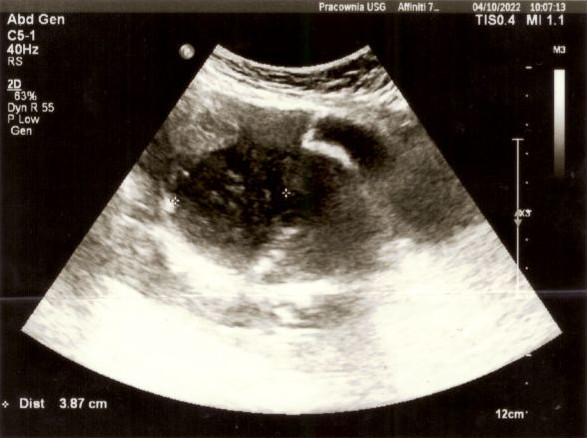

Minął prawie rok od dnia, w którym poszedłem na spotkanie z Wojownikami. Zbliżało się kolejne spotkanie ogólnopolskie, również w Bydgoszczy. Moja małżonka w międzyczasie idzie na badanie, które systematycznie musi powtarzać co ok 6 miesięcy. Jakiś czas temu wykryto u niej polipy na woreczku żółciowym, więc od paru lat musi je kontrolować. Głównie też ze względu na to, że może być obciążona genetycznie (ojciec Karoliny zmarł na raka). Lecz nie to było naszym utrapieniem. Podczas wizyty kontrolnej na USG wyszło coś jeszcze. Oczom lekarza ukazała się duża zmiana na macicy. Doskonale widać ją było na zdjęciu USG. Lekarz zasugerował pilną konsultację ginekologiczną. Gdy usłyszałem te wieści od mojej kochanej żony i obejrzałem zdjęcie USG, zamurowało mnie i nie wiedziałem, co powiedzieć (zmiana miała prawie 6x4cm widać ją na poniższych zdjęciach). Ogarnął mnie smutek i żal.